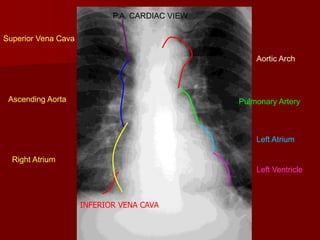

P.A. CARDIAC VIEW

Superior Vena Cava

Aortic Arch

Ascending Aorta

Pulmonary Artery

Left Atrium

Right Atrium

Left Ventricle

INFERIOR VENA CAVA